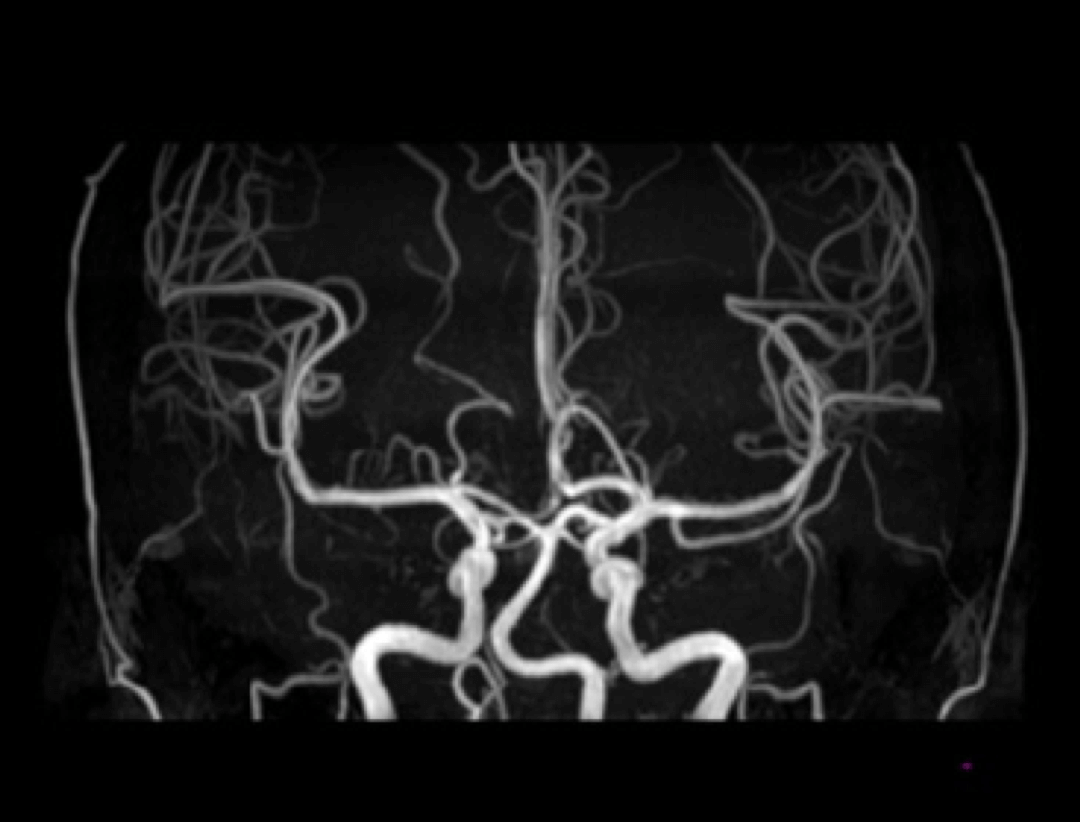

Angiography